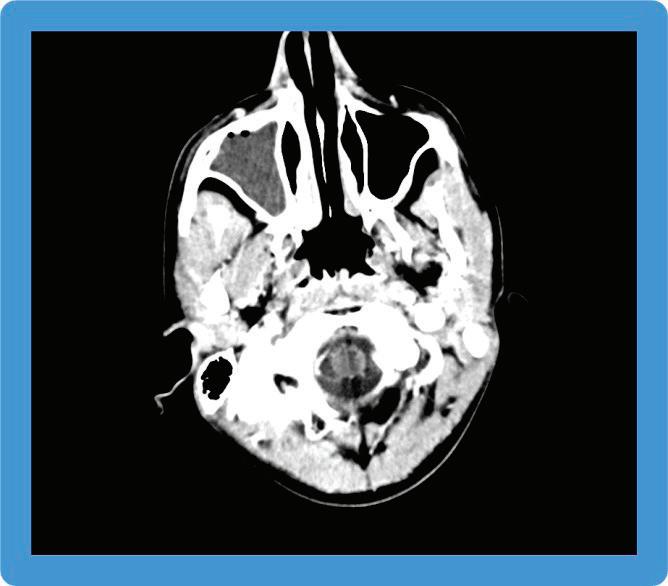

Патогенезата на заболяването, представена съвсем накратко, е следната: Mycobacterium tuberculosis→по въздушно-капков път достига до алвеоларните макрофаги, развива се бактериемия→туберкул→субарахноидално пространство→менингит. Ако от менингите бактерият достигне и до мозъчния паренхим→туберкуломи

абсцеси→ексудат от абсцесите при отварянето им инфилтрира

кортикалните и менингеални кръвоносни съдове и води до мозъчно възпаление и инфаркт. Развива се характерен базален менингит, засягат се предимно III, VI и VII ЧМН и се развива обструктивна хидроцефалия→адхезия + облитериращ васкулит + енцефалит или миелит.

Етиологичната диагноза на туберкулозния менингоенцефалит по обективни причини е възможна в 6-10% от заболелите деца. Поради това диагнозата е комплексно обусловена. Епидемиологичната анамнеза, симптоматиката на базален менингит и характеристиката на ликворния синдром са патогномонични и поставят диагнозата. Абсолютно необходимо е диагностичния процес да продължи с туберкулинов тест на Манту, микробиологично изследване на ликвор (директна микроскопия, посявка на MGIT, PCR real time, BACTEK); SPOT TB; QFT in tube; Рентгеново изследване на белите дробове; КАТ, ЯМР на мозъка.

Беше осъществено Рьо на бели дробове: липсват рентгенови данни за патологични засенчвания в белодробния паренхим двустранно. К.д. синуси – свободни. Сърце и медиастинум – б.о. Контролна КАТ на главен мозък: екстремно разширени вентрикулни отдели на ликворната система. Намален

око

цистерни. Заключение: КТ данни за тежка вътрешна хидроцефалия